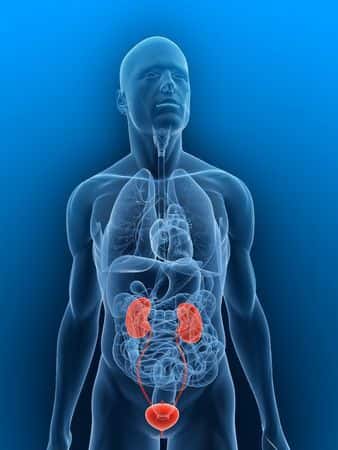

This case takes place in Alaska and involves a fifty-five-year-old male patient who presented to his primary care physician complaining of six month history of hematuria and groin and hip pain. The patient also reported that he was experiencing occasional twitching sensations in the tip of his penis at the time. The physician suggested that the penile twitching sensation may be caused by sacral nerve root irritation. The physician did a work up of the patient for the hematuria and referred him to a urologist. The treating urologist performed a cystoscopy and ordered a CT scan. Both investigations were normal and the urologist did not believe further investigation was warranted and he discharged the patient. The patient continued to experience these symptoms and a second cystoscopy was performed some time later. This revealed an abnormal thickening consistent with a bladder tumor. A cystology report found atypical cells present suspicious for urothelial carcinoma. Subsequently, a transurethral resection of the bladder revealed a large, sessile, poorly differentiated appearing bladder tumor in the right lateral, toward posterior wall. The pathology report revealed high grade transitional cell carcinoma of the bladder with invasion into the muscle. The patient died due to the cancer shortly thereafter. It was alleged that by failing to order serial urine cytology testing despite months of persistent unexplained hematuria, gross and microscopic, the treating urologist did not deliver adequate care.